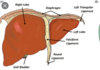

How many main lobes does the liver have?

- 2

- left and right (right is bigger)

What are the superior and inferior borders or the liver called?

- superior = diaphragmatic surface

- inferior = visceral surface

What are the 2 accessory lobes of the liver called?

1 - quadrate

2 - caudate

What is the large white struction on the anterior section of the liver and what role does it have in providing stability to the livers anatomical position?

- falciform

- attaches liver to anterior wall of abdomianl cavity

What is the falciform on the anterior aspect of the liver formed from?

- a fold from the peritoneum

The ligamentum teres (round ligament) is an attachment to the falciform ligament on the anterior section of the liver. What is this a remnant of?